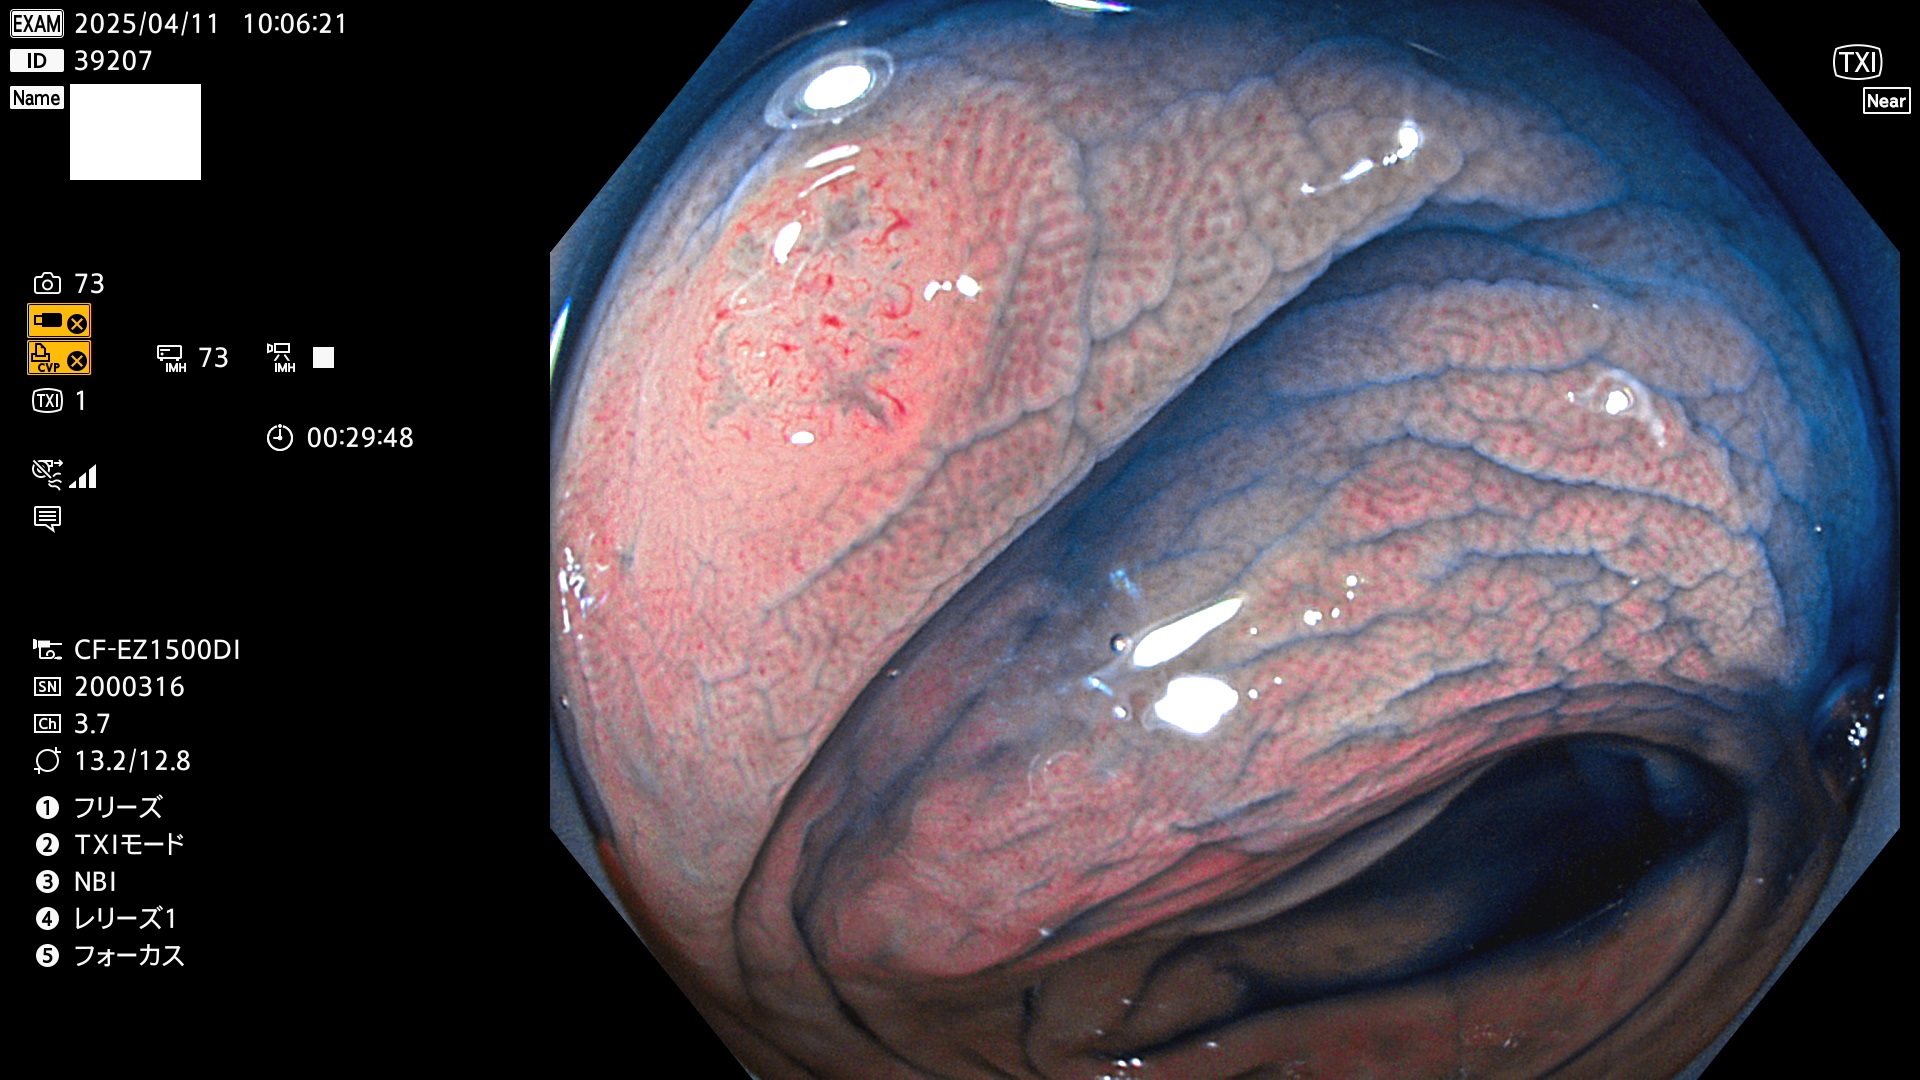

完全に平坦な物をUb、陥凹している物をUcと呼びます。Ubは認識が困難で、Ucはびらん(炎症)と紛らわしいために見落とされやすく、「内視鏡後・大腸癌」の原因になります。

抽出の対象期間 2025年4月10日〜4月13日の4日間(48件の検査)11個 (4/48=23%)

びらんと鑑別の困難なUc型腺腫